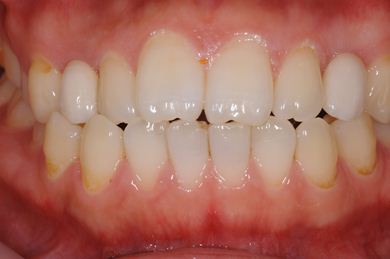

治療後

• 治療後